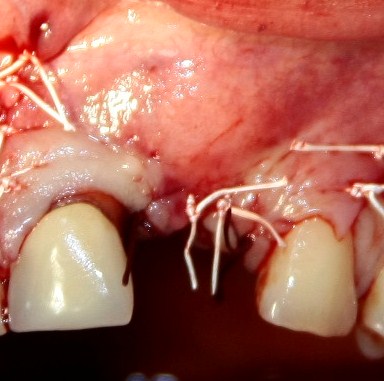

Трансплантация десны, аугментация лунки

Для определения размеров будущего мягкотканного аутотрансплантата мы использовали пародонтологический зонд. С помощью него мы выбрали донорскую зону (бугор верхней челюсти или небная сторона альвеолярного отростка верхней челюсти в области моляров), с помощью скальпеля получили необходимый по размеру аутотрансплантат (мягкотканный лоскут для пересадки).

Если вы когда-нибудь видели подобные операции, то наверняка обращали внимание на порядок действий — сначала устанавливаются имплантаты, затем укладывается графт и только потом фиксируется мягкотканный аутотрансплантат. Для удобства в этом и похожих клинических ситуациях мы поменяли порядок действий:

Сначала мы провели и зафиксировали деэпителизированный соединительнотканный аутотрансплантат (ССТ). Для этого мы сформировали тоннель и использовали ортодонтическую проволоку в качестве проводника. Подробнее об этой методике можно почитать здесь>>.